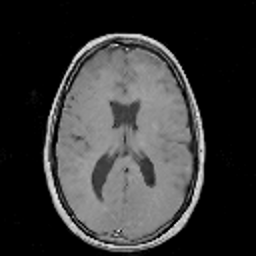

In this subsection, the MRI images from the built-in MRI dataset available in the MATLAB® toolbox have been used as test subjects. Specifically, the denosing algorithms have been tested using the axial slices number 4, 7 and 16 (shown in Figures 5, 5 and 5, respectively), which represent a spectrum of different cerebral structures. For quantitative comparison, simulated data have been obtained by subjecting the original test images to various levels of Rician noise.

Figure 5: (a) Test slice #4, (b) Test slice #7 and (c) Test slice #16 of the MATLAB® MRI database.